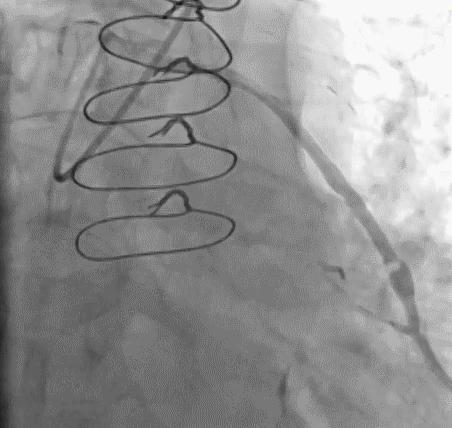

(3)冠状动脉静脉桥血管

首选导管:JR4.0;

其他导管:AL 1.0;AR 1.0

操作:升主动脉造影,寻找静脉桥血管

➢ CASE 3

AL1.0

➢ CASE 4